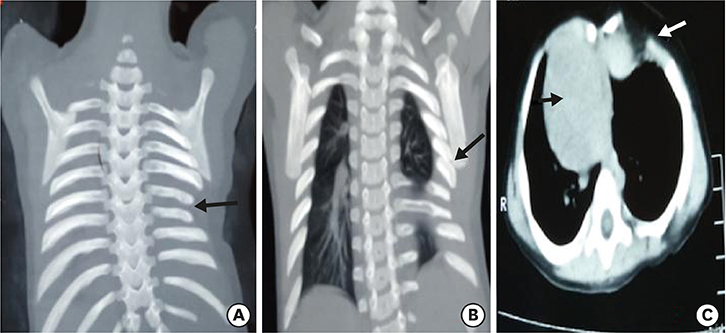

Fig. 1) was suspicious of bowel loops or stomach herniating into the left hemithorax. With a working diagnosis of congenital diaphragmatic hernia (CDH)/hiatus hernia, the patient was planned for emergency surgery. The patient was explored through a left subcostal incision. There was no diaphragmatic defect. Although the left diaphragm was higher up in position, it was normal, thick and muscular and not thin and redundant, as in diaphragmatic eventration. There was no paraesophageal or sliding hernia. The spleen was found to be free from its ligamentous attachments. On palpation, of the left chest wall, the lower ribs and costal cartilages were absent along with a portion of the lower sternum. There were deficiency and absence of attachment of pectoral muscles in that region creating a 4×3 cm size muscular defect, which was repaired with non-absorbable sutures. The post-operative period was uneventful and the child was discharged 5 days later. During follow up, the child was evaluated with CT chest with 3D reconstruction (

Fig. 2) which was suggestive of dextrocardia, partially fused left 5th and 6th ribs, hypoplastic 7th and 8th ribs, left lung smaller in volume as compared to the right lung, sternal defect and scoliosis of the dorso-lumbar spine. To rule out any associated syndromic conditions, ultrasound (USG) of kidney, ureter, bladder (KUB), 2-dimensional (2D) echocardiography (ECHO) and gastroesophageal reflux (GER) scan were done, which were normal. The child was doing well during the last follow up at 8 months age.

Fig. 2 Computerized tomography with 3-dimensional reconstruction showing hypoplastic 7th and 8th rib (A, black arrow), fused 5th and 6th ribs (B, black arrow), dextrocardia (C, black arrow) and costal cartilage defect (C, white arrow).